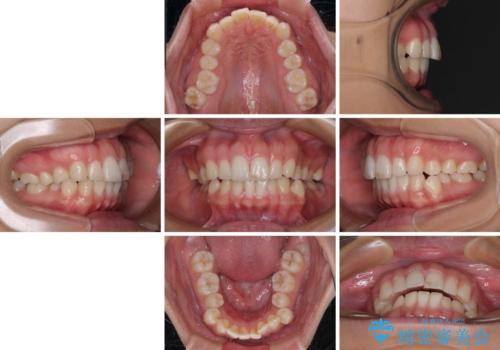

【モニター】突出した前歯 補助装置を併用したインビザライン矯正

- 上下前歯が非接触となり、前方に突出していることを気にして来院された患者様です。

咬合力が強く、全体的に歯がすり減っているため、インビザライン単独での上顎歯列移動は困難と判断し、補助装置により上顎歯列を後方移動させ、その後インビザラインにて仕上げていくこととしました。

補助装置なしでも改善できる可能性はありましたが、補助装置で確実性を上げ、短期間できっちりと仕上げることができました。